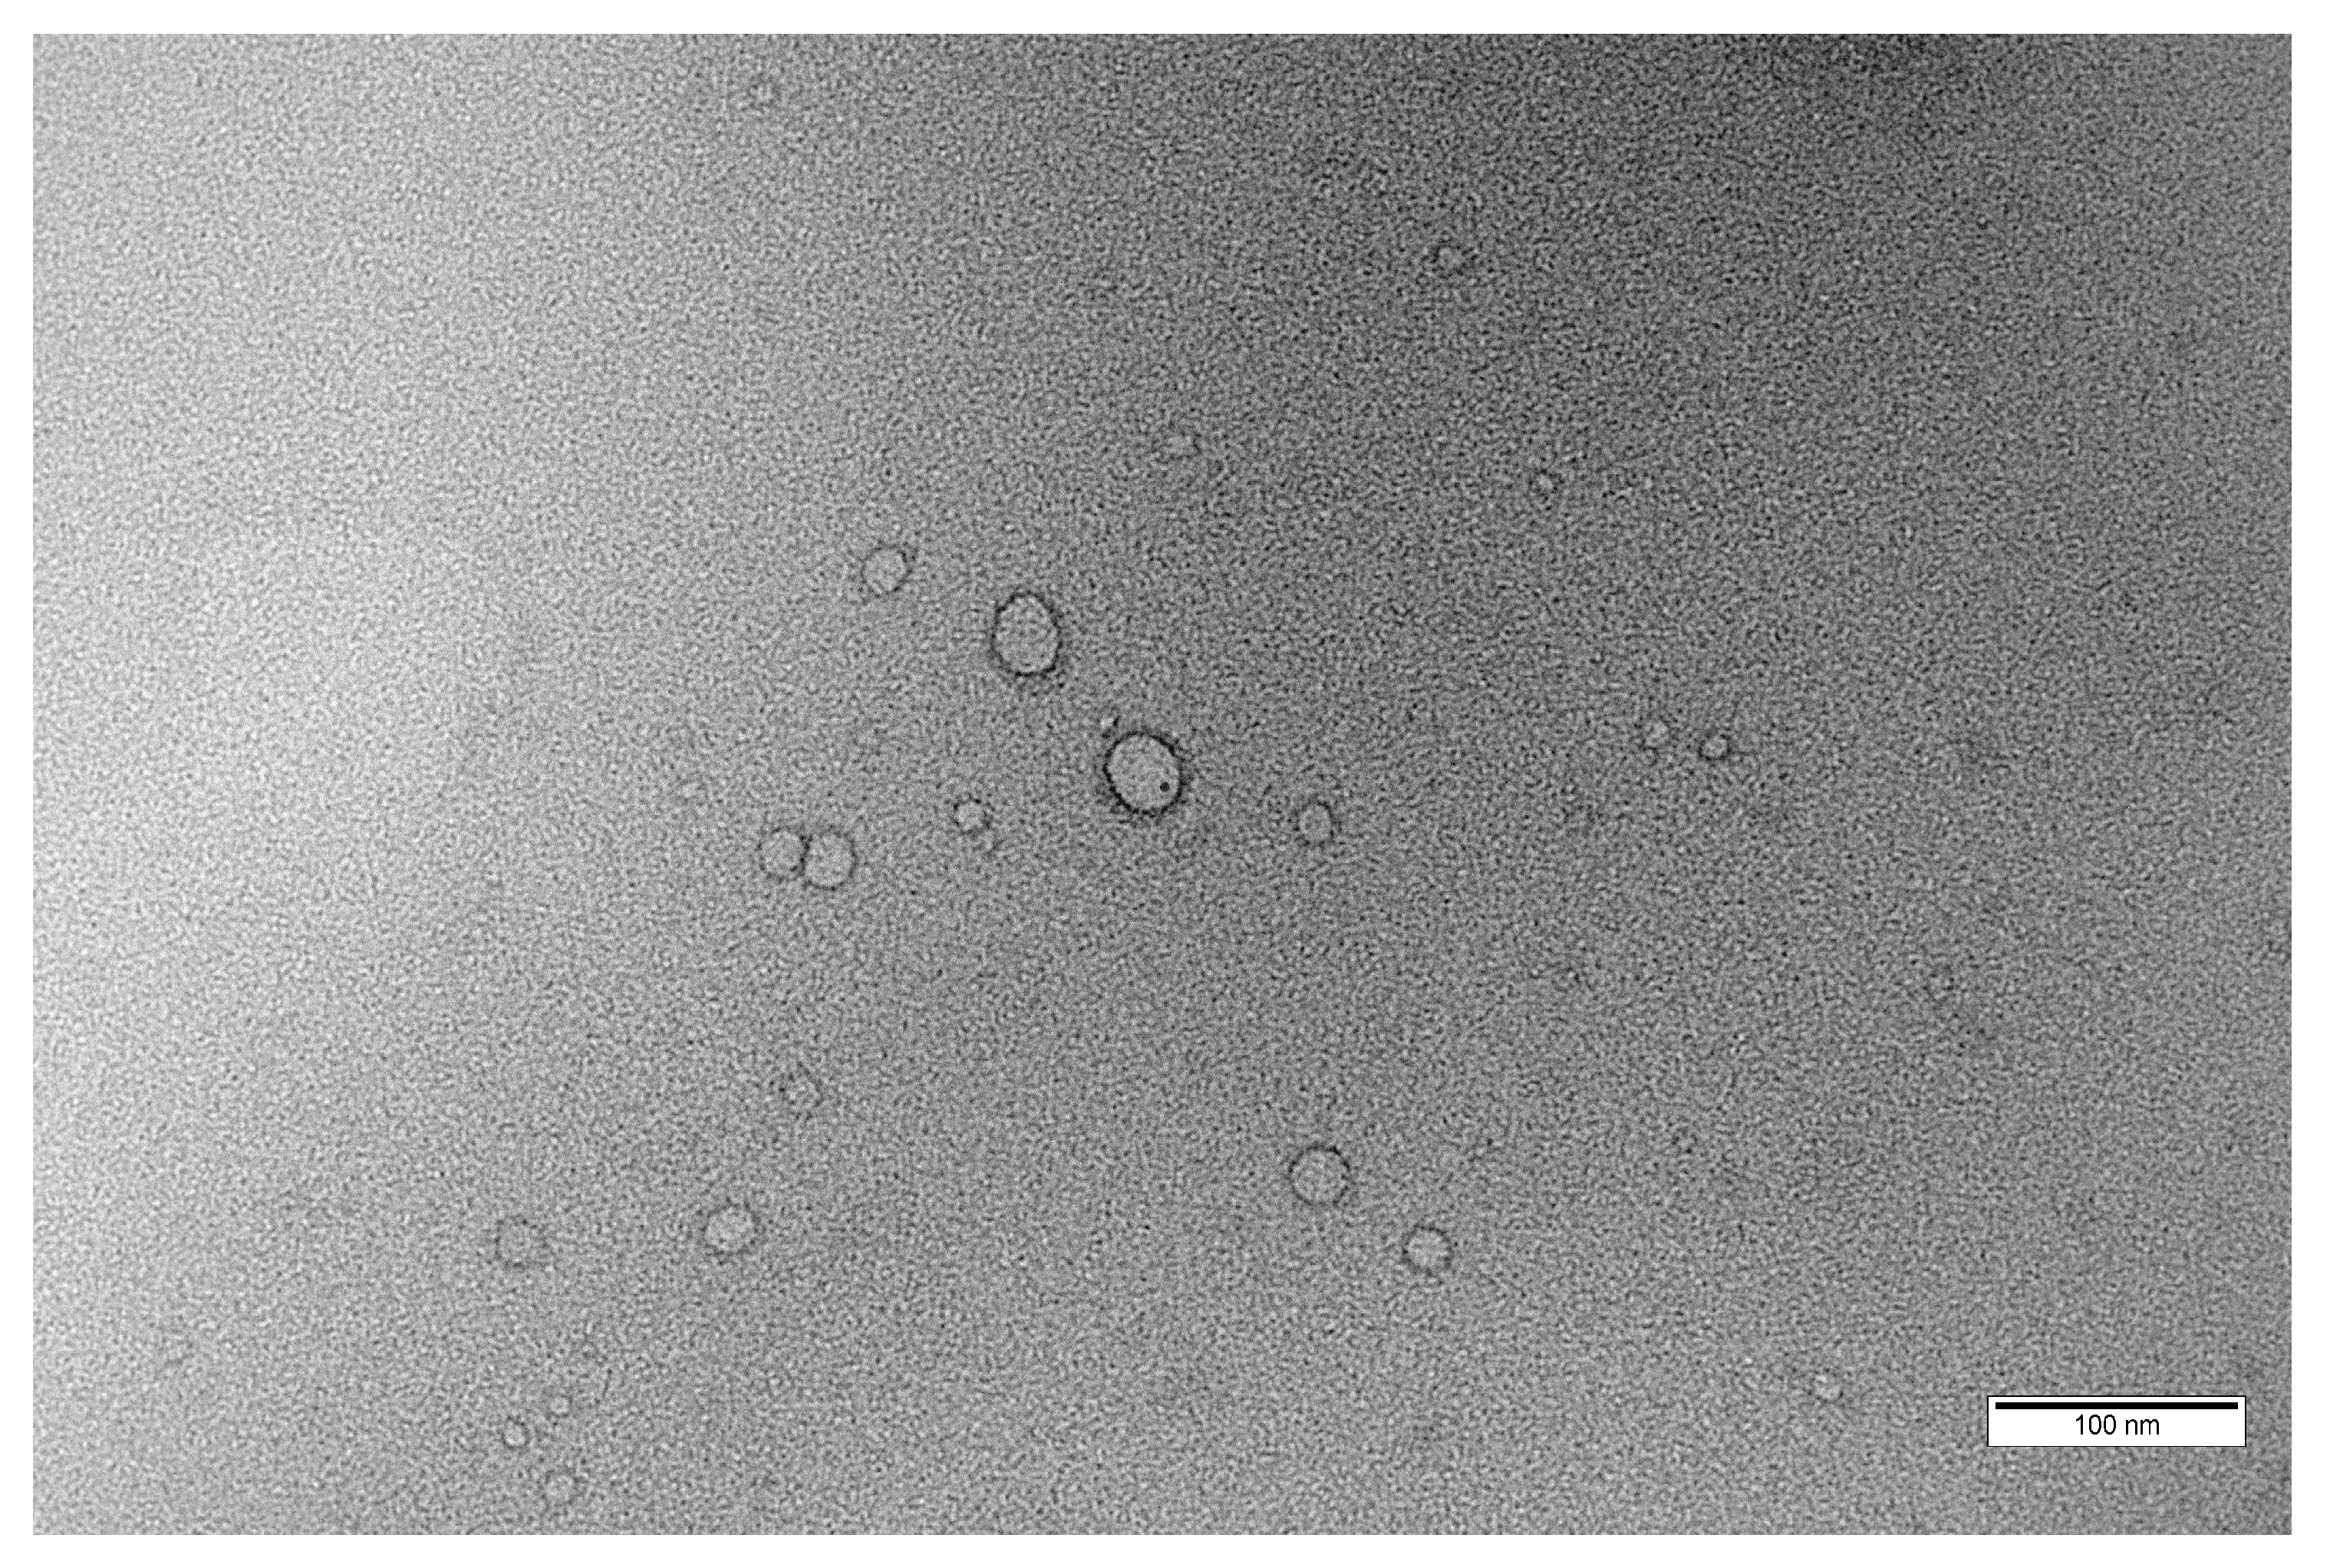

2.2.2. Morphology, Particle Size and Zeta Potential Measurements

3.1. Preparation and Characterization of Blank Polymersomes